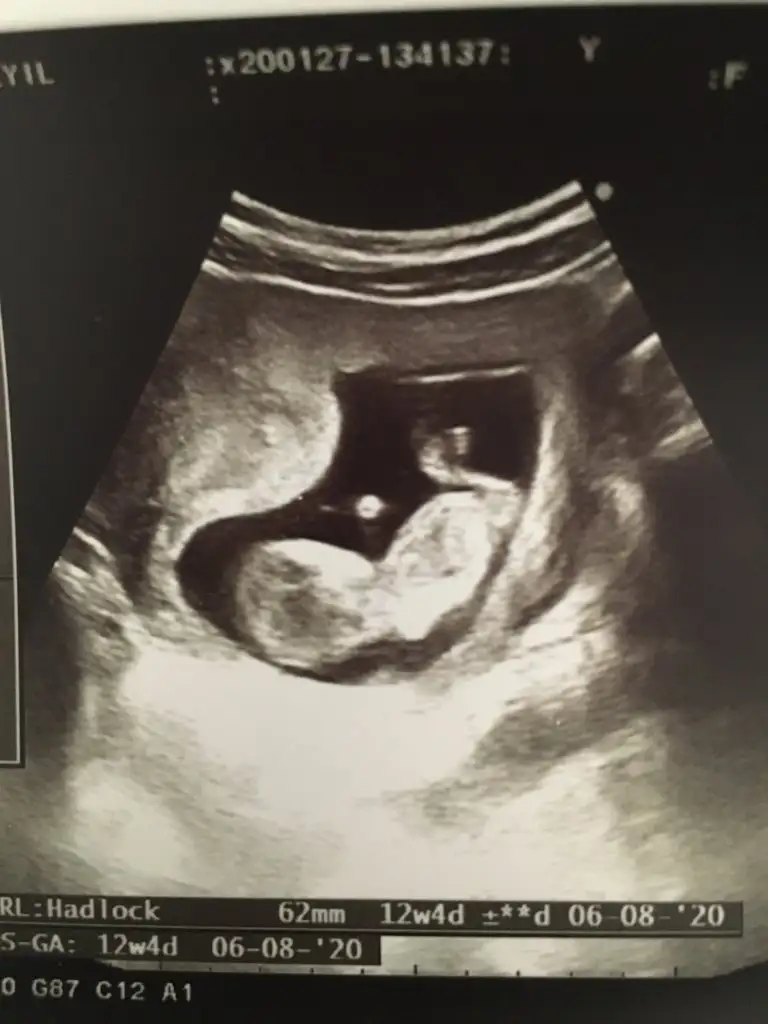

Buda benim bebişim 12 haftalık cinsiyeti sizce nedir😊

45CFB82A-2675-4DCE-89D8-BF5501063824.webp